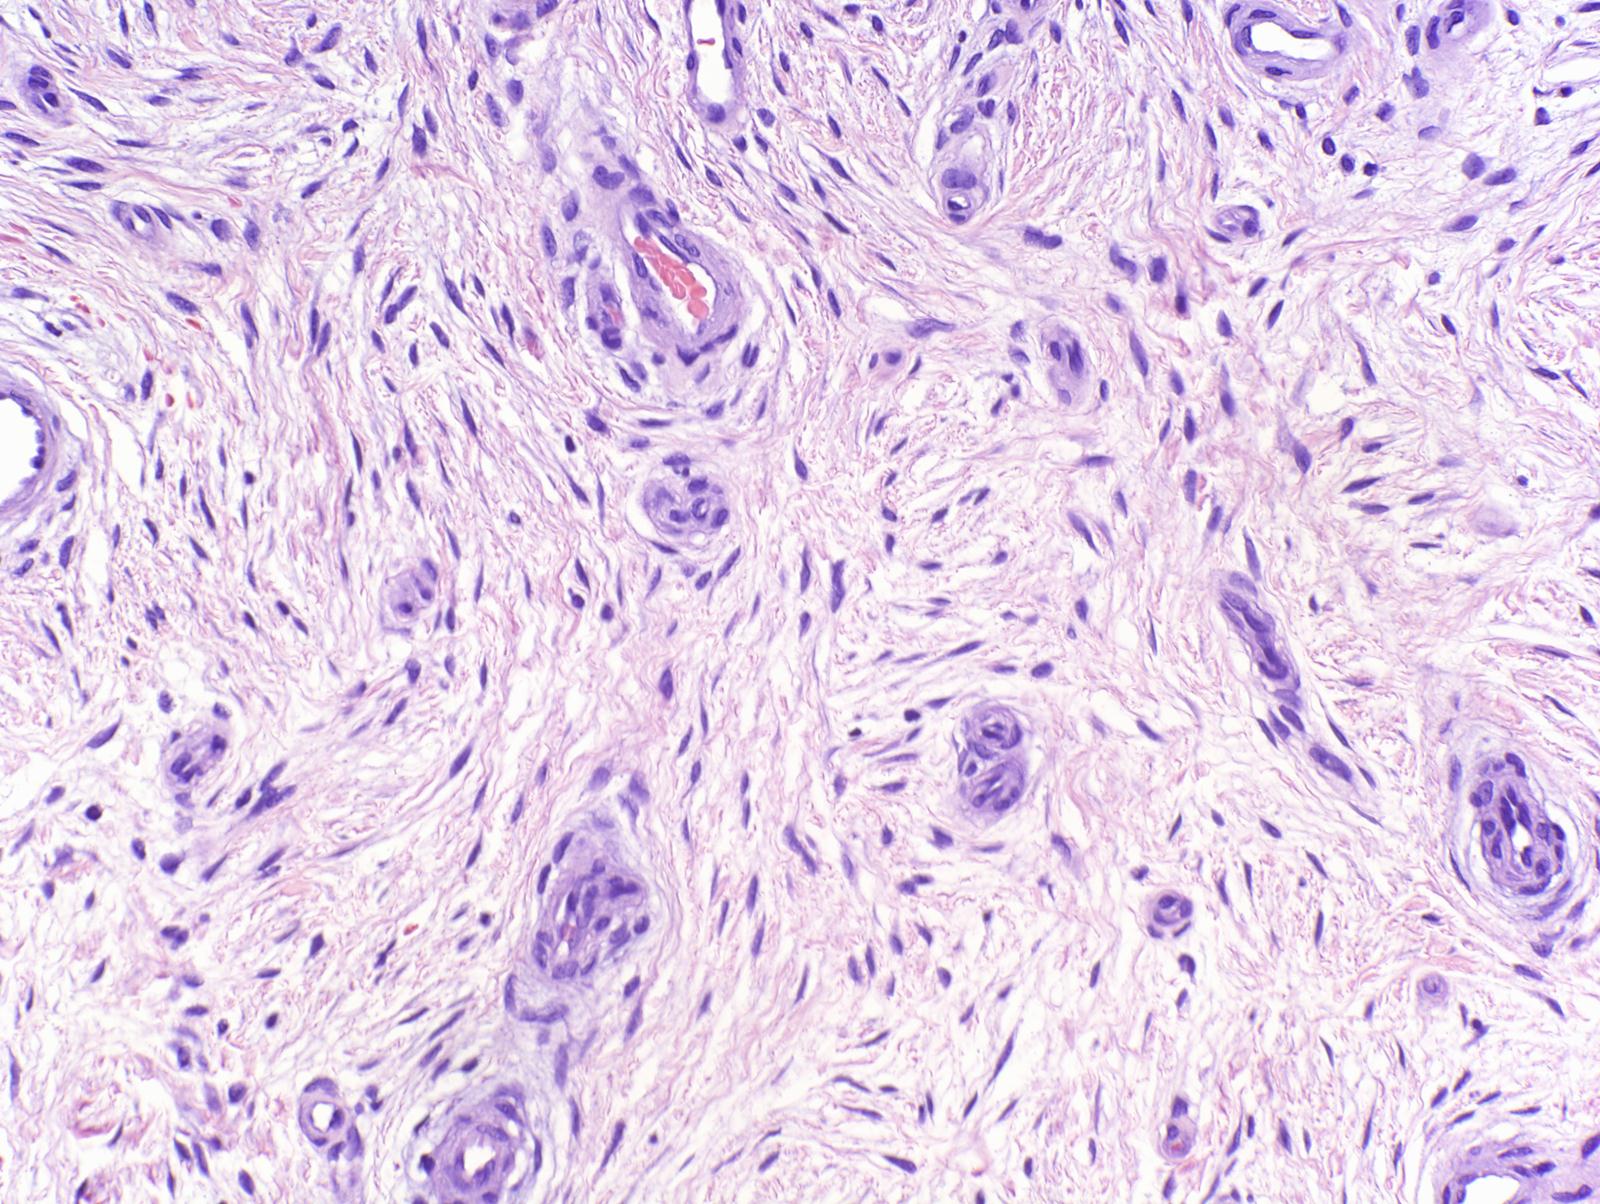

The lesion was shave-excised and the base cauterized. Pathology showed a nodular dermal lesion comprised of fibromyxoid stroma with stellate to spindle-shaped fibroblasts and traversed by prominent vascular channels. (Photomicrographs 2x, 4x, 10x, 20x, 40x)

Diagnosis: Superficial Acral Fivbromyxoma